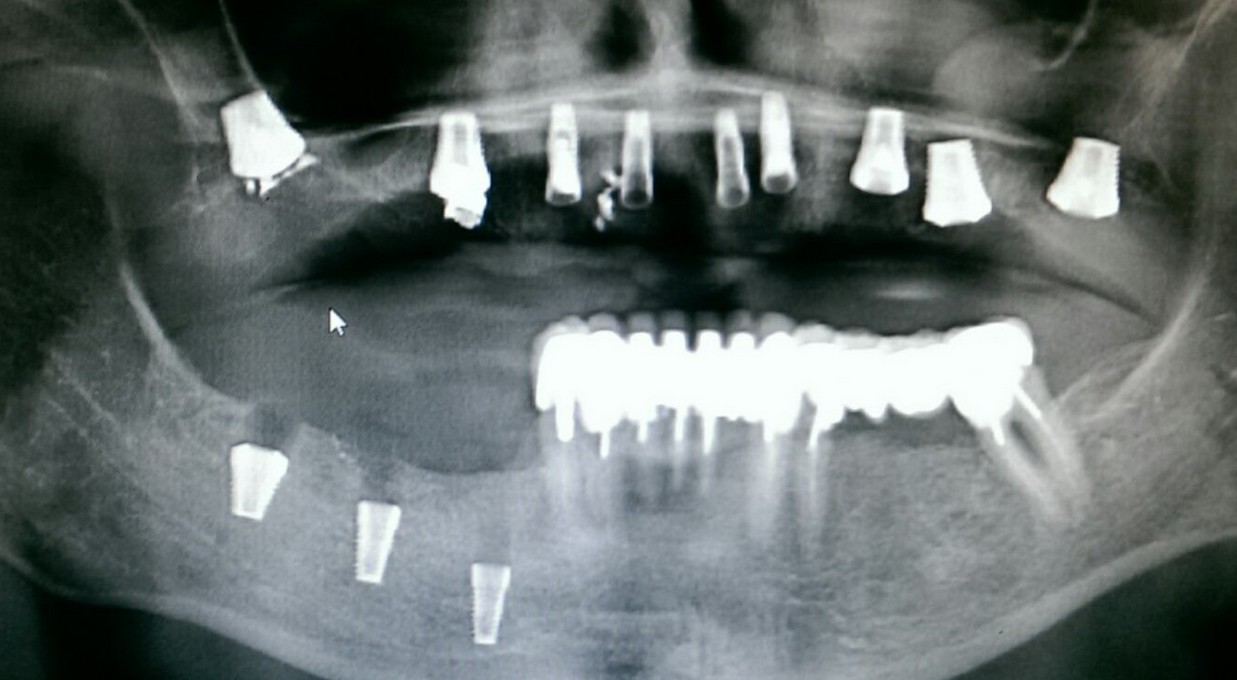

Исследование на рентгене после имплантации зубов

Раздел: Снимки-откровения